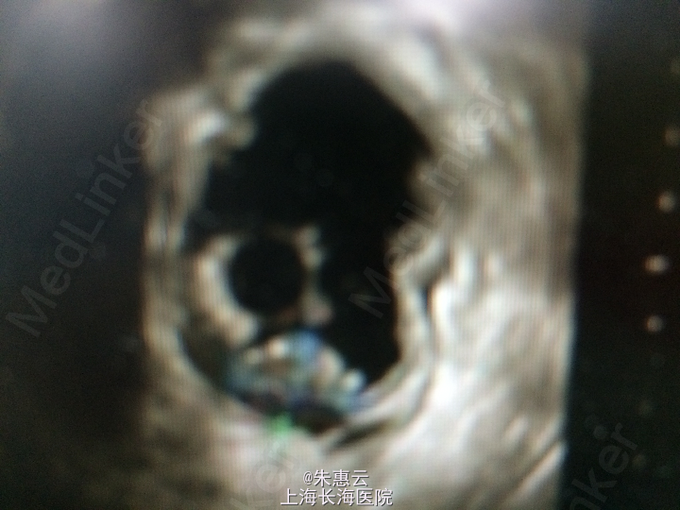

患者,男,61岁 主诉:上腹部不适2月 现病史:因牙痛自服消炎药(具体不详)后,出现上腹部不适,无压痛及放射痛,无发热,无呕血、黑便,就诊于我院行胃镜检查示:胃窦部粘膜隆起性质待查,糜烂性胃炎,十二指肠球部霜斑样溃疡。病理:(胃窦)中度慢性非萎缩性胃炎,HP(+)。超声内镜示:胃粘膜隆起性病变(畸胎瘤可能)。 既往史:2005年及2013年因“胃溃疡”出现黑便,当地医院给与止血、补液等治疗后,患者至今未发黑便。

专科检查:未见明显异常。 辅助检查:胃镜检查示:胃窦部粘膜隆起性质待查,糜烂性胃炎,十二指肠球部霜斑样溃疡。病理:(胃窦)中度慢性非萎缩性胃炎,HP(+)。超声内镜示:胃粘膜隆起性病变(畸胎瘤可能)。 住院期间主要检查结果:血、尿、粪三大常规,肝肾功能电解质、肿瘤指标等未见明显异常。

诊断:胃窦粘膜下隆起 诊疗经过:入院后行胃ESD术,术中于粘膜隆起区下方见较大溃疡,结合患者HP(+),故先行抗HP治疗。